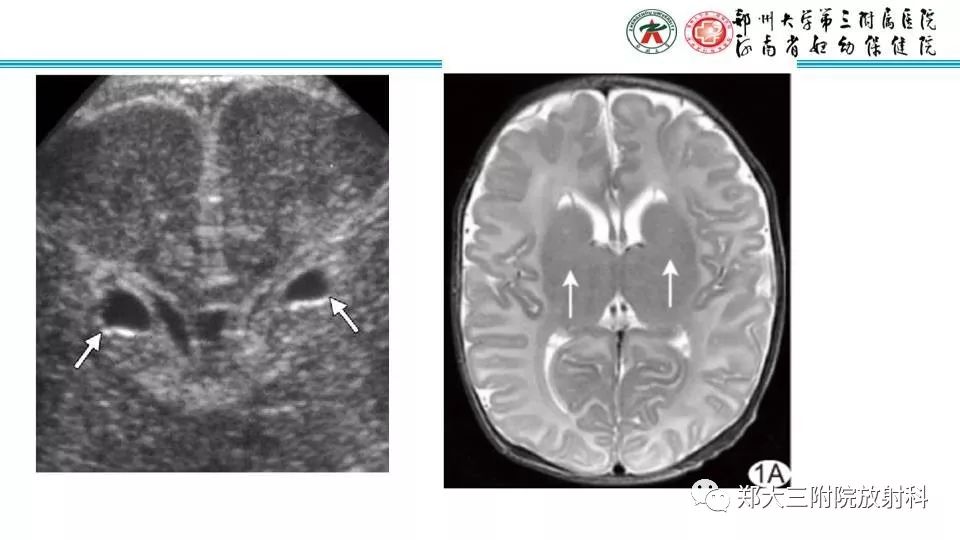

【PPT】室周假性囊肿-3